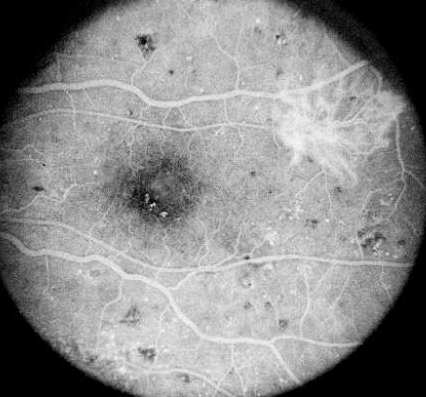

Diabetic retinopathy gives a combination of both hyper/

hypofluorescence. Several pathologies are seen in this frame:

Hypofluorescence: retinal haemorrhage (1) and ischaemia (2).

Hyperfluorescence: microaneurysms (3) and neovascularization (4)

In addition, there are IRMA (5) between the retinal artery and vein and venous beading (6)